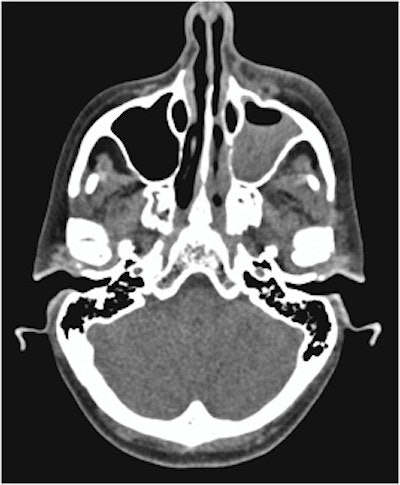

A 54-year-old woman lost vision in one eye after developing orbital cellulitis following a tooth extraction, according to a case report published in Advances in Oral and Maxillofacial Surgery.

An axial CT scan shows opacification of the woman's left maxillary sinus with marked soft tissue swelling of her left infraorbital. Image courtesy of Ghasemi, et al. Licensed under CC BY 4.0.

CT scans revealed swelling and fluid around the woman's eye and partial opacification of her maxillary sinus and aided in the diagnosis of the rare but deadly bacterial infection odontogenic orbital cellulitis. Surgery treated her infection, but the woman has complete vision loss in her left eye.